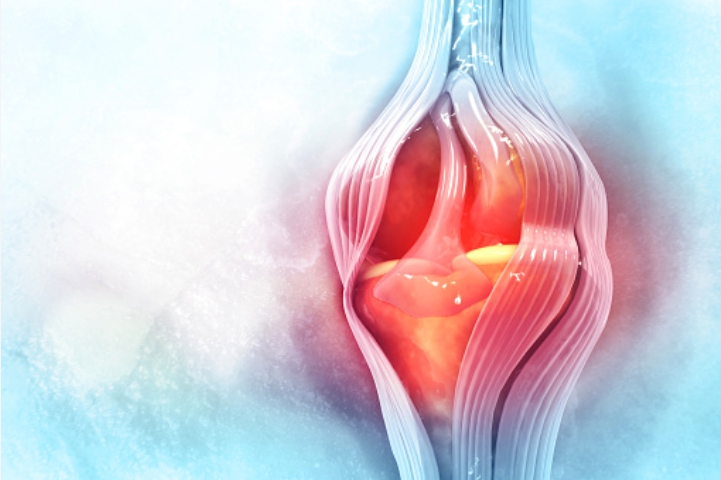

4. MSM의 효능 항염 효과

msm은 염증을 억제하데 탁월한 효능이 있다고 해요. 염증이 우리 몸에 발생하면 MSM은 염증 성분 자체를 억제하여 증상 회복에 도움을 준다고 합니다.

전신 염증과 관련된 신호 단백질인 TNF-α 및 IL-6과 같은 사이토카인의 생성을 감소시켜 염증 반응을 수치를 억제하는 작용을 하여 우리몸에 항염 효과가 있습니다.

염증으로 인해 부어있는 관절의 활막액의 크기를 감소시켜 관절염 환자의 통증에 효과가 있다고 합니다.